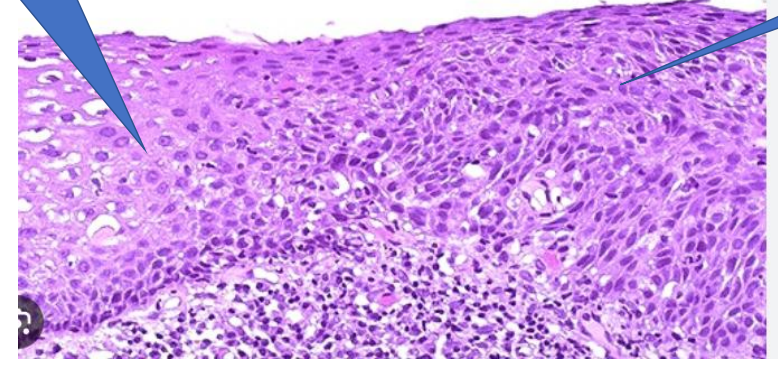

cellular and nuclear pleomorphism

abnormal mitotic figures

1- abnormal mitotic figure

2- chromatin clumping

3- nuclear pleomorphism

4- increased nuclear cytoplasmic ratio